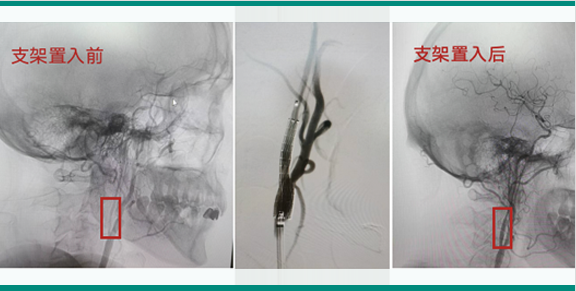

顱內(nèi)狹窄的球囊擴(kuò)張和支架置入術(shù)